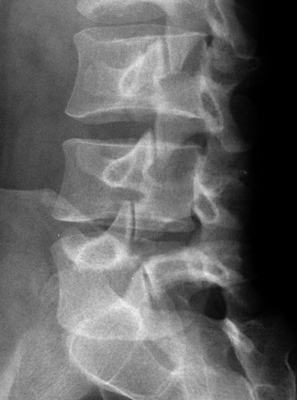

On the oblique view of the lumbar spine, the outline of a dog can seen. The parts of the dog are as follows: the transverse process-the nose; the pedicle-the eye; the pars interarticularis-the neck; the superior articular facet-the ear; the inferior articular facet-the front leg. A break in the neck of the dog, or a dog collar, corresponds to a fracture in the region of the pars interarticularis, which is specific for spondylolysis. It is important to recognize as it is a cause of low back pain. A. Normal. B. L5 Pars defect.

Oblique lumbar spine - Click on the image for a larger versionAOblique lumbar spine - Click on the image for a larger versionB